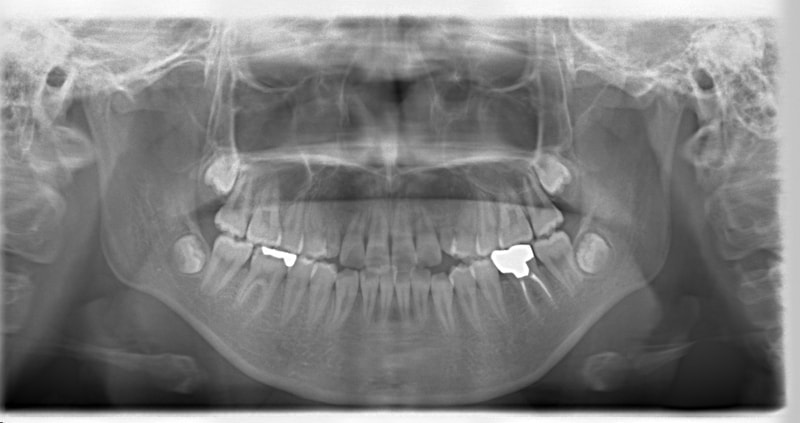

症例紹介

先天欠如歯両側上顎3番

治療法:フルパッシブブラケット:T21

治療前